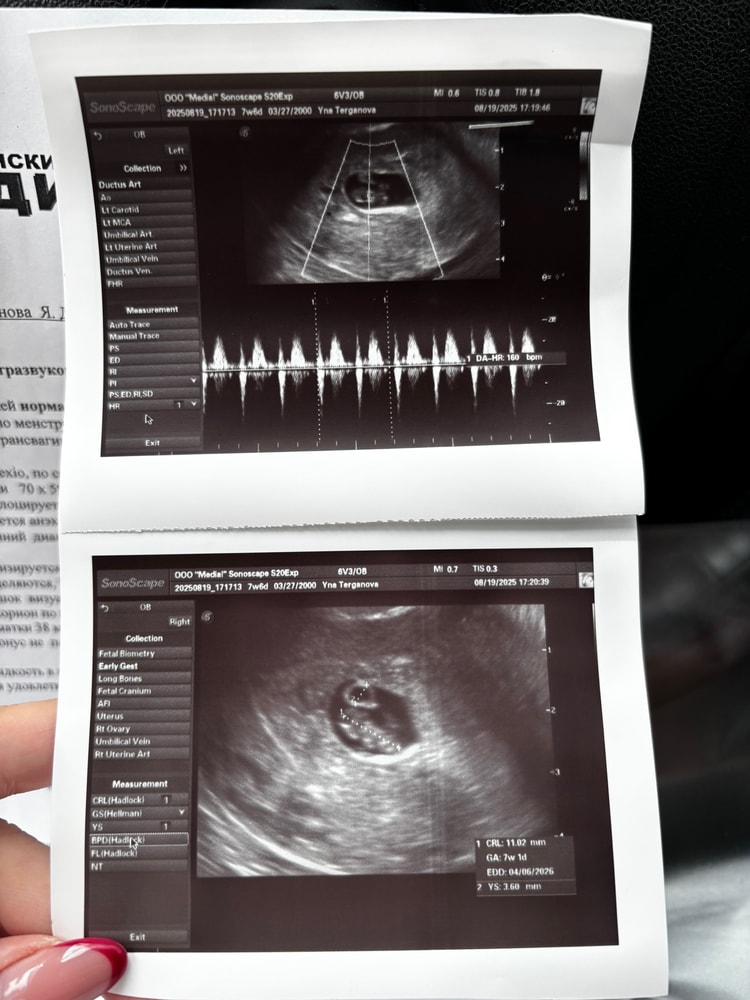

Всем привет. Сегодня 7+6. Последнюю неделю бывает по капельке-две крови на салфетке. На прошлом узи 6+5 тонуса и гематомы не было. Подскажите, это очень серьезно?